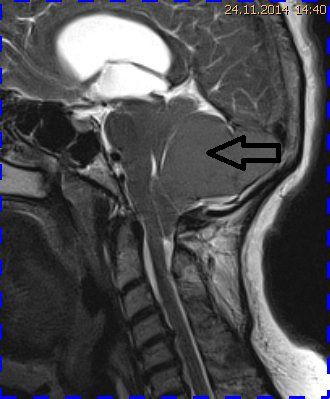

Abb. 4.1 MRT (T2 TSE, 1,5 T) sagittal: Kompression des Kleinhirns durch ein großes Tentoriummeningeom (Pfeil) mit Verlagerung der Tonsillen in das Foramen magnum

Natürlich kann eine Dislokation der Kleinhirntonsillen in das Foramen magnum auch andere Ursachen haben, wie das Fallbeispiel 2 zeigt (Abb. 4.1 bis 4.3). Eine 57-jährige Patientin hatte ein monströses Tentoriummeningeom entwickelt, das zu einer Verlagerung der Kleinhirntonsillen nach kaudal führte. Die postoperativen Verlaufskontrollen zeigten die Repositionierung der Tonsillen in der hinteren Schädelgrube.